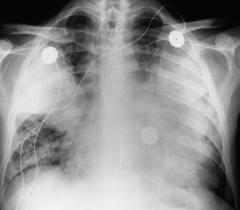

Các bệnh nhân SRAT hoặc sốt rét có biến chứng nên được quản lý tại các trung tâm chăm sóc tích cực. Họ có thể được hỗ trợ về mặt huyết động (haemodynamic support) và quản lý vấn đề suy hô hấp cấp (ARDS), đông máu nội mạch rải rác, suy thận, co giật, nhiễm trùng tái diến (intercurrent) nặng nề gồm cả nhiễm khuẩn gram (-) hoặc sốc nhiễm trùng máu.

Các trẻ em châu Phi bị SRAT thường từ các biến chứng: hôn mê (SRATTN), suy hô hấp nặng (ARDS), hạ đường huyết. Thậm chí ngay khi đã điều trị tại bệnh viện rất tốt, có đến 20% trẻ bị tử vong. SRAT ở người lớn tương tự như trên trẻ em châu Phi, nhưng khác nhau ở các vùng khác. Người lớn cũng có thể rơi vào hôn mê và hạ đường huyết hoặc thiếu máu nặng. Ngược lại với trẻ em, người lớn cũng hình thành các biến chứng nghiêm trọng đột ngột cho chức năng thận (suy thận cấp), suy hô hấp (ARDS) như trẻ em nhưng nghiêm trọng về mức độ ngang nhau (phù phổi cấp). Trong số các bệnh nhân người lớn nhập viện bị SRAT, con số tử vong có lên đến 20%.